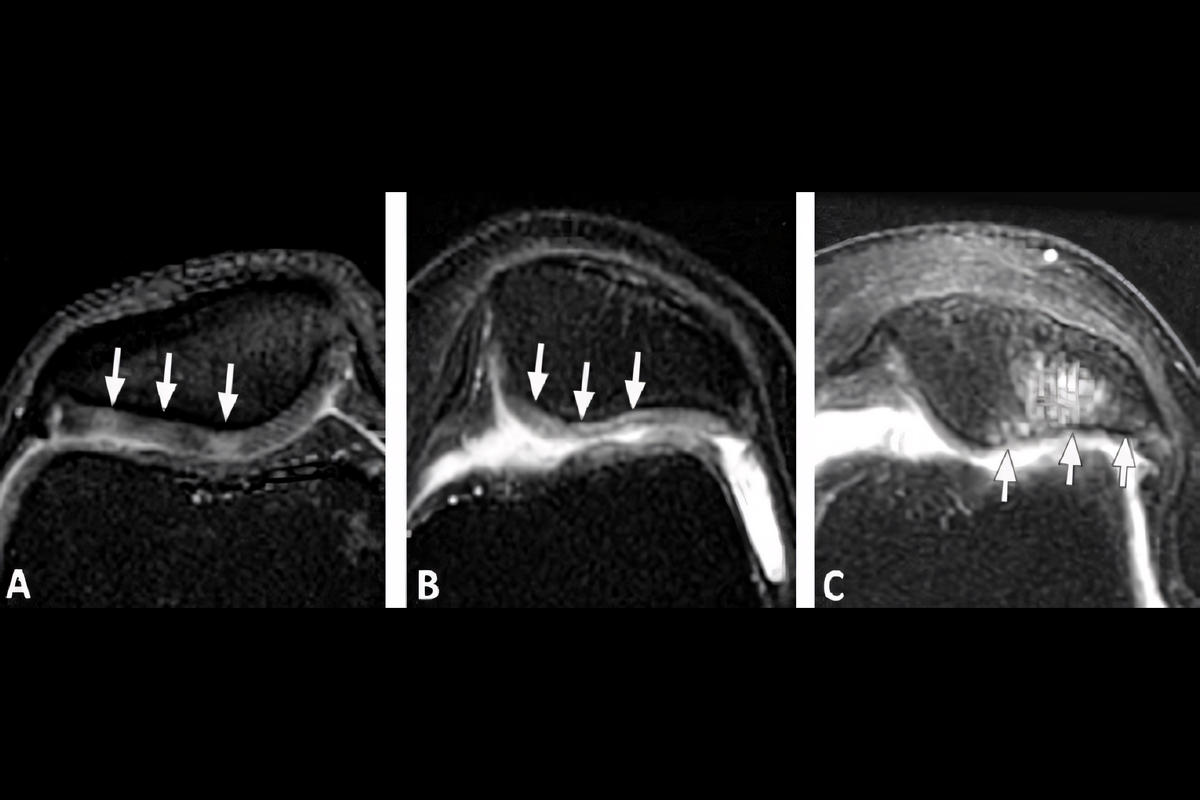

Μαγνητική τομογραφία (MRI) για εκτίμηση της βλάβης του χόνδρου

Η MRI είναι ιδιαίτερα χρήσιμη για την αξιολόγηση του βαθμού εκφύλισης.

Η ταξινόμηση κατά Outerbridge αποτελεί διεθνώς αποδεκτό σύστημα εκτίμησης της βλάβης χόνδρου:

Βαθμός I: Μαλάκυνση και οίδημα χόνδρου

Βαθμός II: Επιφανειακές ρωγμές μικρής έκτασης

Βαθμός III: Βαθιές ρωγμές με ανώμαλη επιφάνεια

Βαθμός IV: Πλήρης απώλεια χόνδρου με έκθεση υποχόνδριου οστού

Η ταξινόμηση καθοδηγεί την επιλογή θεραπείας.

Modified Noyes & Stabler classification για MRI